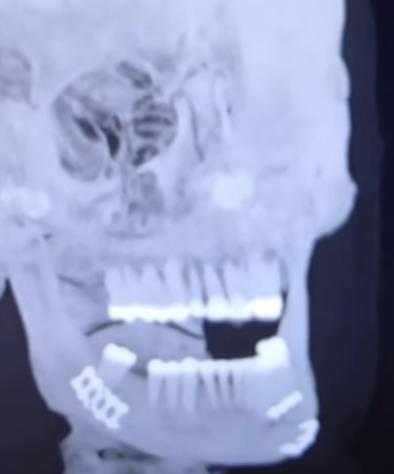

Más tarde, Jake Paul subió una imagen en sus redes sociales en la que aparece en una camilla, acompañado por su hermano Logan, y confirmó con una radiografía que Joshua le partió la mandíbula.

"Doble fractura de mandíbula. Denme al Canelo en diez días", bromeó el estadounidense en referencia al mexicano Saúl 'Canelo' Álvarez, con el que también le gustaría probarse en el ring.

Esta mañana del sábado, Paul se volvió a dirigir hacia sus seguidores: "La cirugía salió bien, gracias por todo el cariño y apoyo. Dos placas de titanio en cada lado. Me extrajeron algunos dientes. Tengo que tomar solo líquidos durante siete días".

El norteamericano también subió esta radiografía para mostrar como ha quedado su boca tras la pelea.